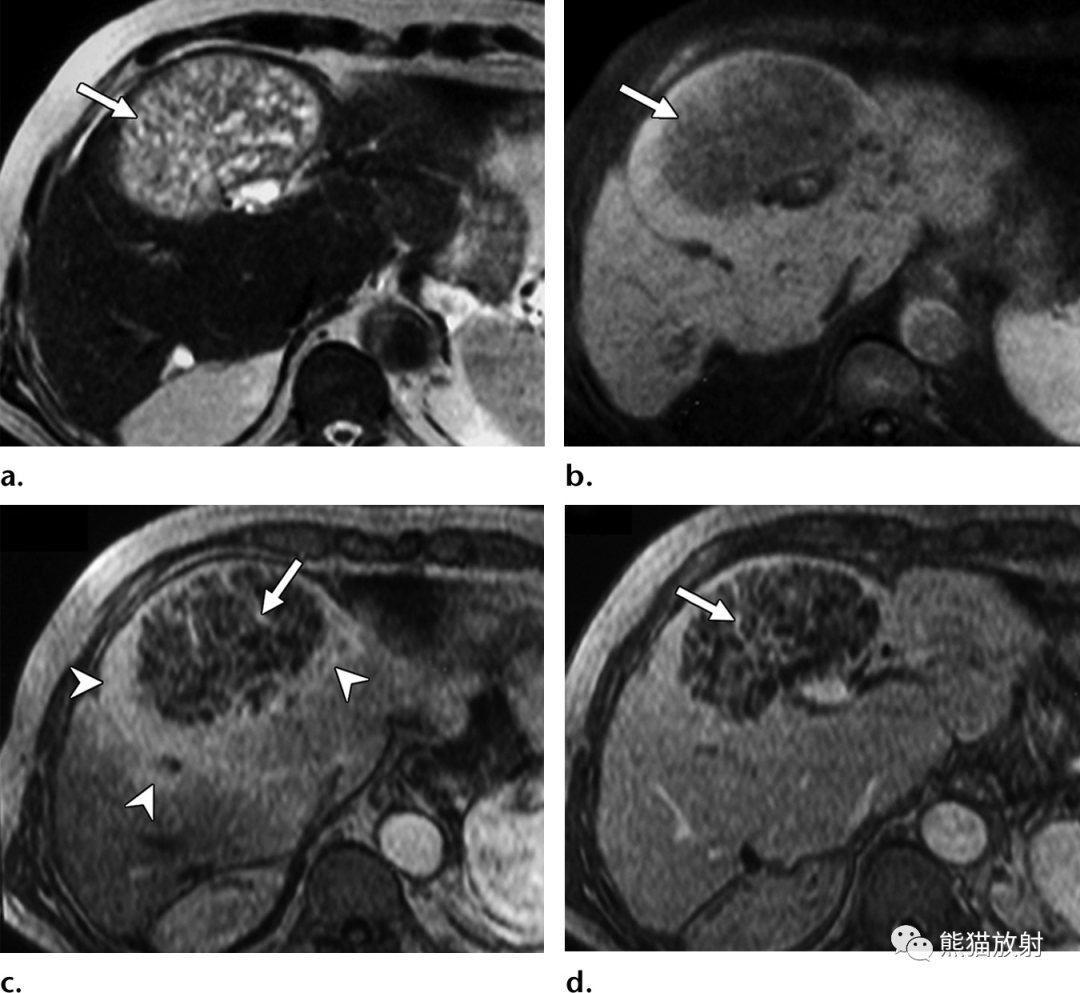

65岁男性,因急性坏疽性胆囊炎发生化脓性肝脓肿。(a)轴位T2WI显示脓肿壁的双靶征,表现为围绕脓肿内部高信号内容物的等低信号内层(箭头)和中等高信号外层(箭)。注意胆囊颈部嵌顿的低信号结石 (*)。(b)轴位对比增强动脉期脂肪抑制T1WI图像显示内层早期强化(箭头)和邻近节段性肝实质充血。(c)轴位对比增强延迟期图像显示内层和外层延迟强化(箭)。

55岁男性,肝移植后1年,肺炎克雷伯菌脓肿。(a)轴向对比增强CT图像显示化脓性肝脓肿内有气体(箭)。(b)轴位梯度回波反相T1WI图像显示脓肿内无信号的气体(箭),与结肠内气体的表现相似(*)。(c)同相位T1WI显示由于气体磁化率效应增强脓肿内出现光晕伪影(箭),在邻近结肠中也观察到伪影(*)。(d)DWI (b = 800s/mm2) 显示由于水扩散受限,脓肿内部呈高信号(箭)。(e) 相应的ADC图显示扩散系数降低,表现为脓肿内的低信号(箭)。

“绿松石征”和肝脓肿一过性节段性强化。(a)轴位T2WI显示肝左叶肝脓肿,内部高信号并大量树枝样间隔(箭),表现类似绿松石。(b)轴位脂肪抑制T1WI平扫显示低信号局灶性肝脏病变。(c)对比增强动脉期病灶周围高强化(箭头)和内部分隔强化(箭)。(d)延迟期可见内部分隔持续强化(箭)。脓肿内容物抽吸培养物有肺炎克雷伯菌生长。